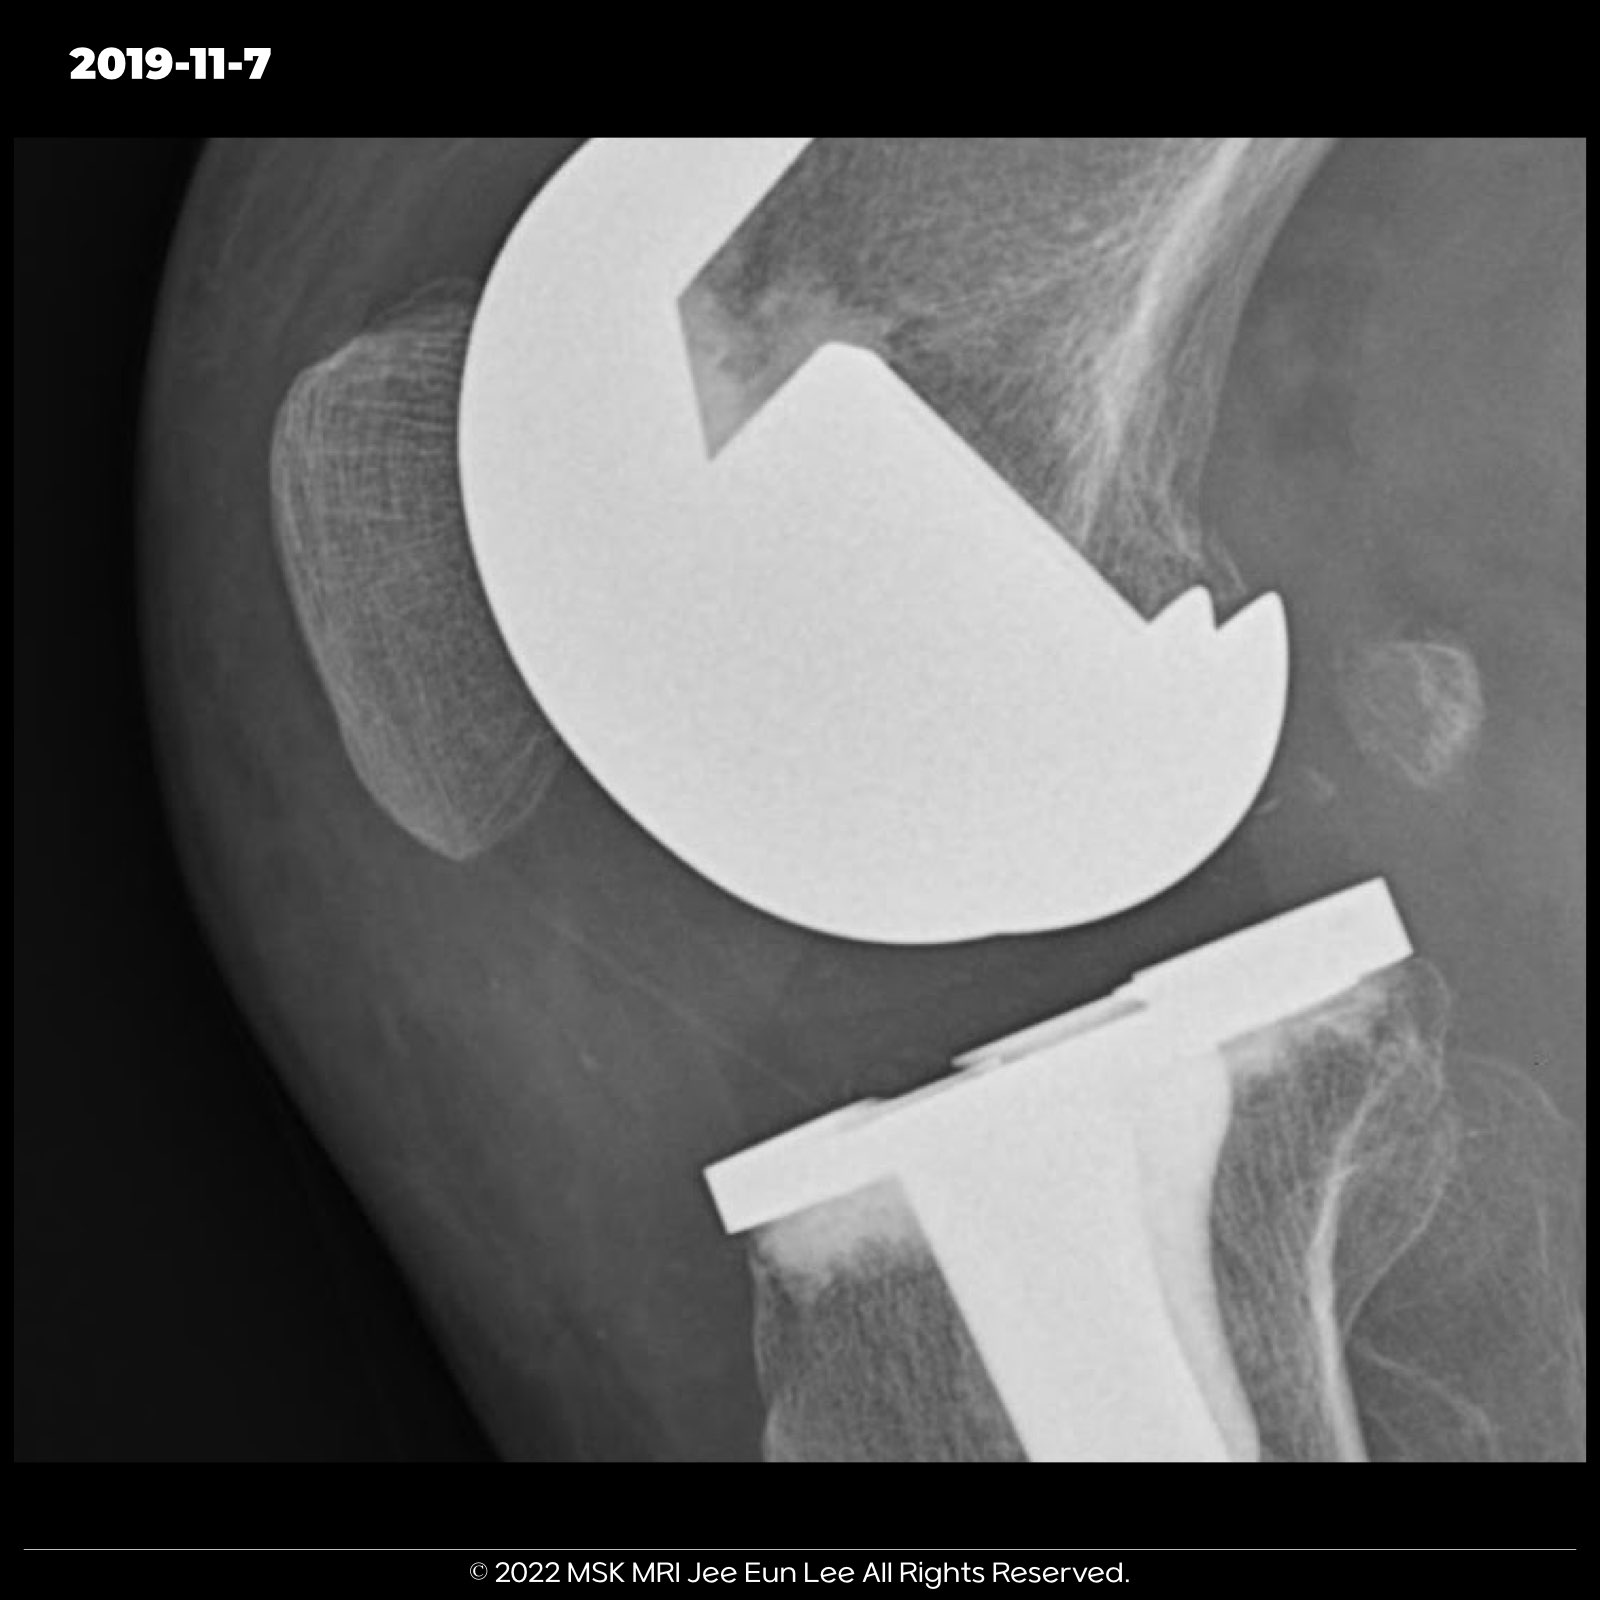

Complete dislocation of the polyethylene insert in fixed-bearing total knee arthroplasty.

Dislocation of a polyethylene insert Mechanism of Dislocation (DPI in TKA) Proposed Cause

| Impingement on soft tissues or osseous structures | Impingement of the insert on soft tissues or osseous structures can lead to DPI; a case with a large posterior osteophyte was observed, suggesting it may be responsible for dislocation |